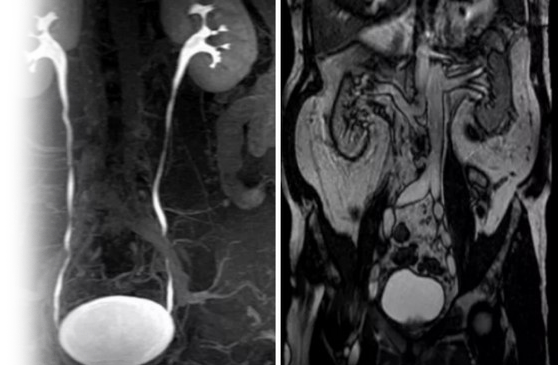

Магнитно-резонансная томография мочевыделительной системы с контрастной урографией – важный метод исследования с введением контрастного вещества, который позволяет визуализировать органы мочевыделительной системы и окружающие мягкие ткани.